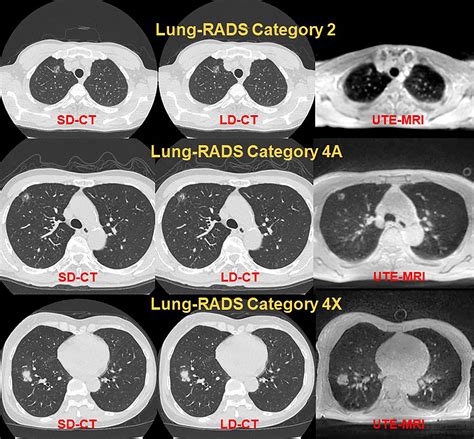

The classification system uses a numerical scale to indicate the likelihood of malignancy and the appropriate management step for each patient. Each category is designed to balance the benefits of early detection with the risks associated with invasive testing. Below is a breakdown of how the classification system is structured under the current standards:

• Category 0: Incomplete assessment. Requires prior imaging for comparison or additional views to resolve technical limitations.

• Category 1: Negative. No nodules are identified, or existing nodules are benign (e.g., completely calcified). Annual screening is recommended.

• Category 2: Benign appearance. Nodules with a very low probability of malignancy. Annual screening is recommended.

• Category 3: Probably benign. Requires a short-term follow-up CT scan, usually within six months, to monitor for stability.

• Category 4: Suspicious. Further diagnostic evaluation, such as PET/CT, biopsy, or surgical consultation, is often required based on specific criteria.

Diagnostic Criteria and Management Summary

The system relies on precise measurements of nodule diameter. Because solid and subsolid (ground-glass) nodules behave differently, the management recommendations in the Lung-RADS 2022 framework differentiate between these types. The following table provides a simplified overview of how findings are typically managed:

Lung-RADS Category Assessment Management Recommendation

Category 1 Negative Annual Screening

Category 2 Benign Annual Screening

Category 3 Probably Benign 6-month Follow-up CT

Category 4A Suspicious 3-month Follow-up CT or PET/CT

Category 4B/X Very Suspicious PET/CT, Biopsy, or Consultation